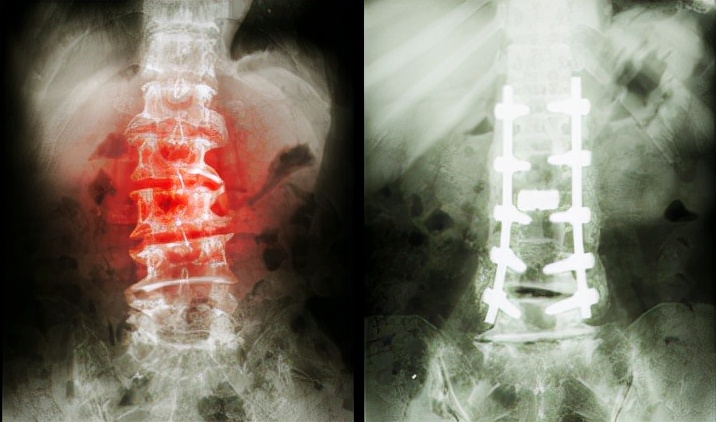

为了自己的健康张大姐急忙去了医院 , 经过缜密的检查和拍片 , 医生告知张大姐患上了严重的腰间盘突出 , 第4、5节腰椎同时突出 。 张大姐非常震惊 , 自己平时身体还可以怎么突然就患上了这种病呢?